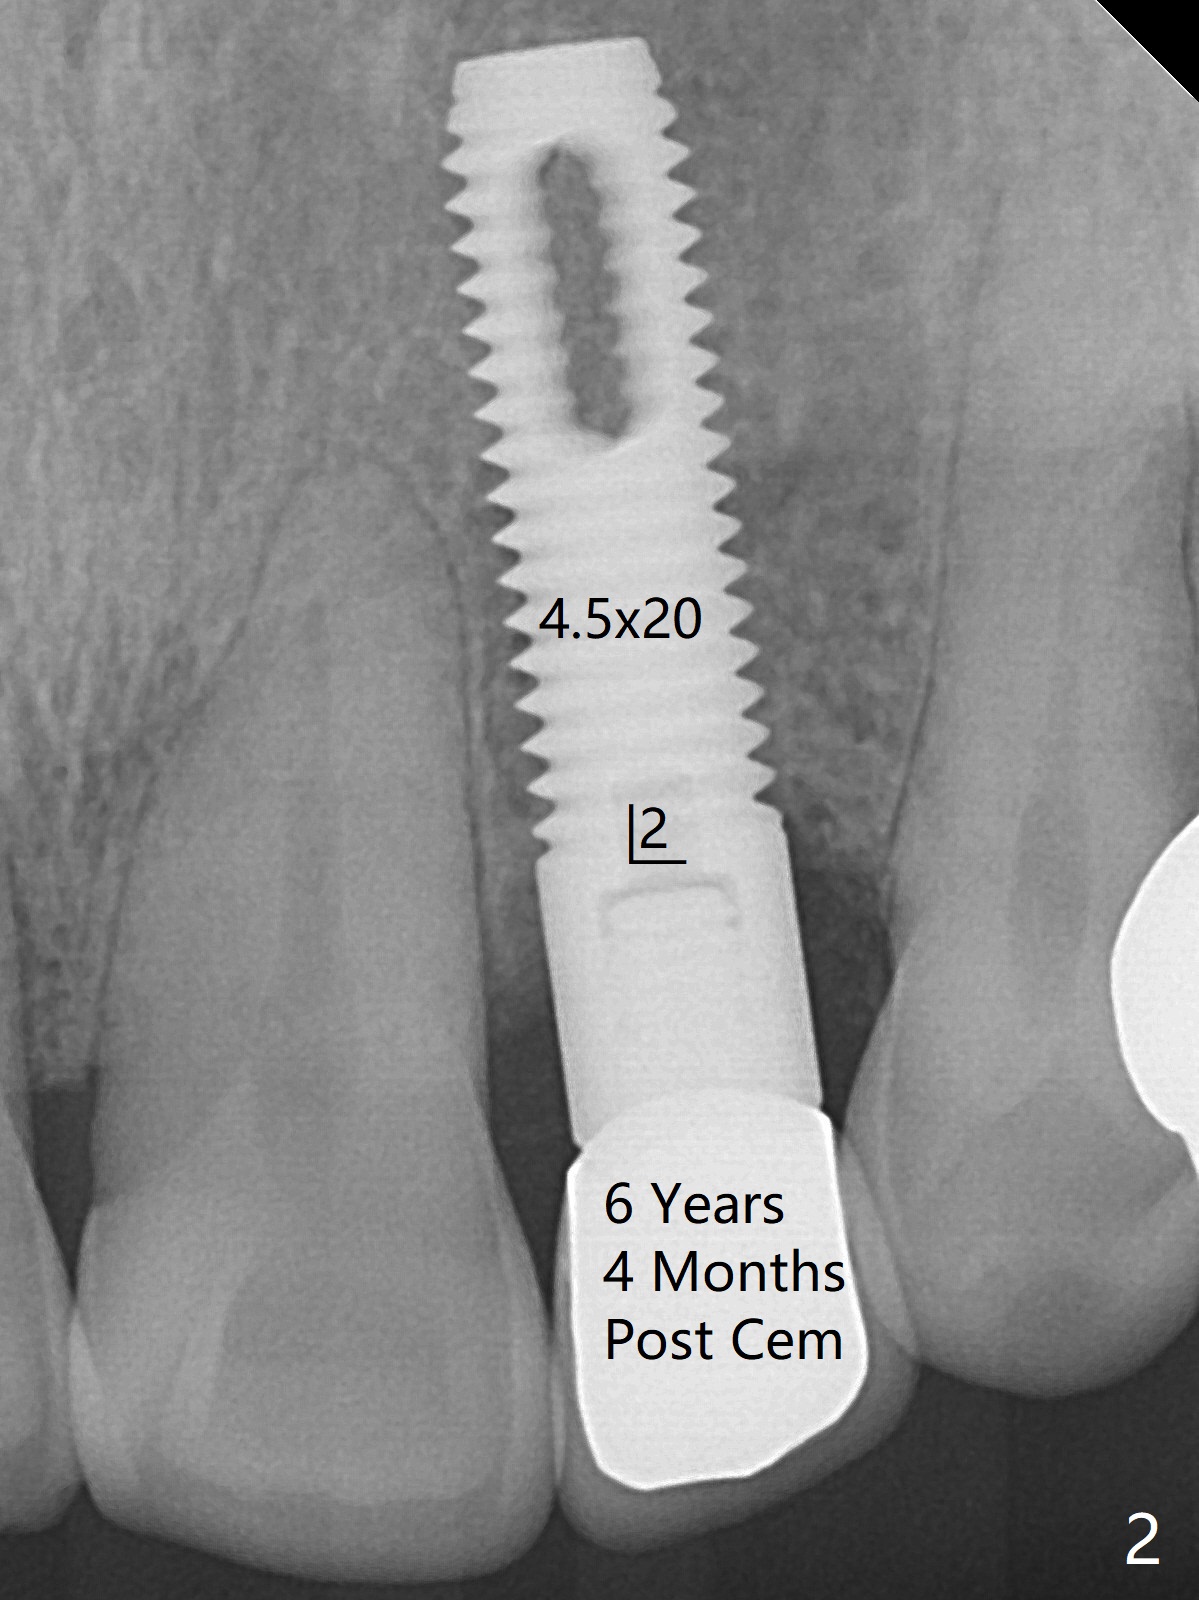

68岁男要求拔除右上2松动牙(图一),尽管近远中空间大,不能象左上2种大植体(图二,五)。右上2骨质吸收严重,植体应该植入深,牙龈厚(6毫米,图三,四),需要长基台,放置粘性骨粉修复骨质缺失。PRF膜好像用处不大,PRF上清液适当多用于制作粘性骨粉。准备牙周洁治器和Endogain,让骨粉与邻牙牙根结合。